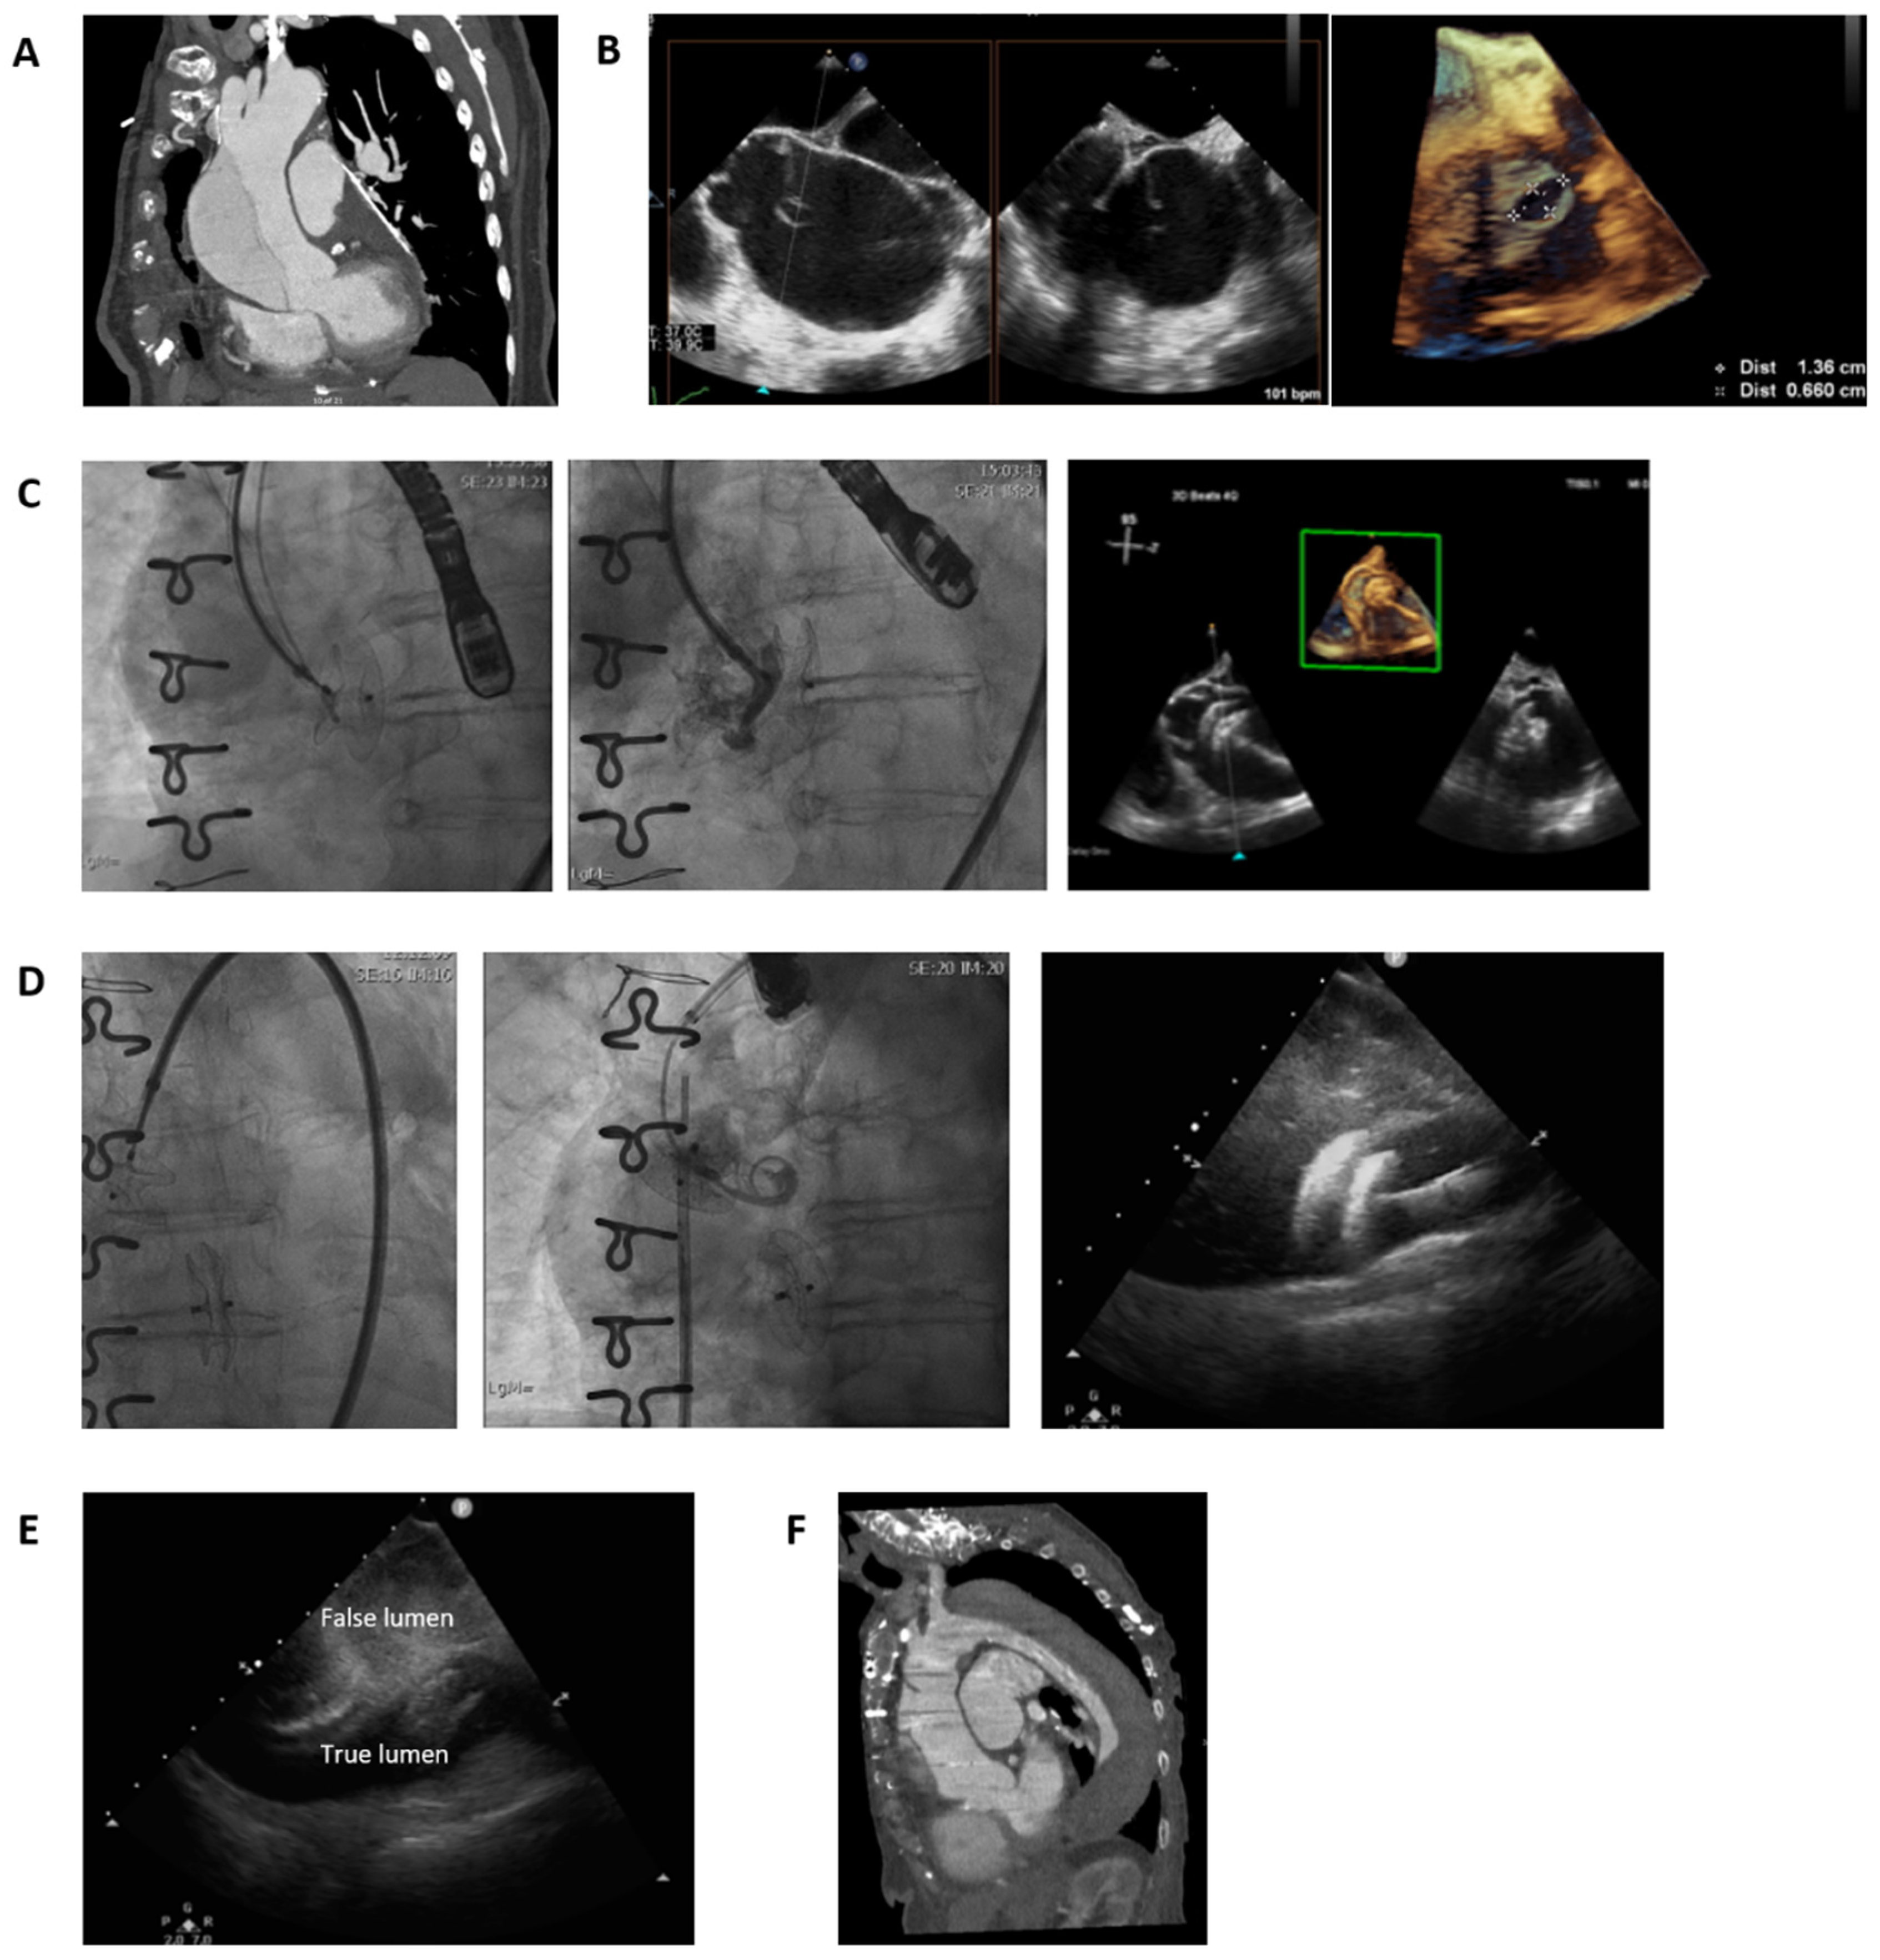

Percutaneous Treatment of Type A Aortic Dissection Using Atrial Septal Defect Occlusion Device

2. Case Presentation